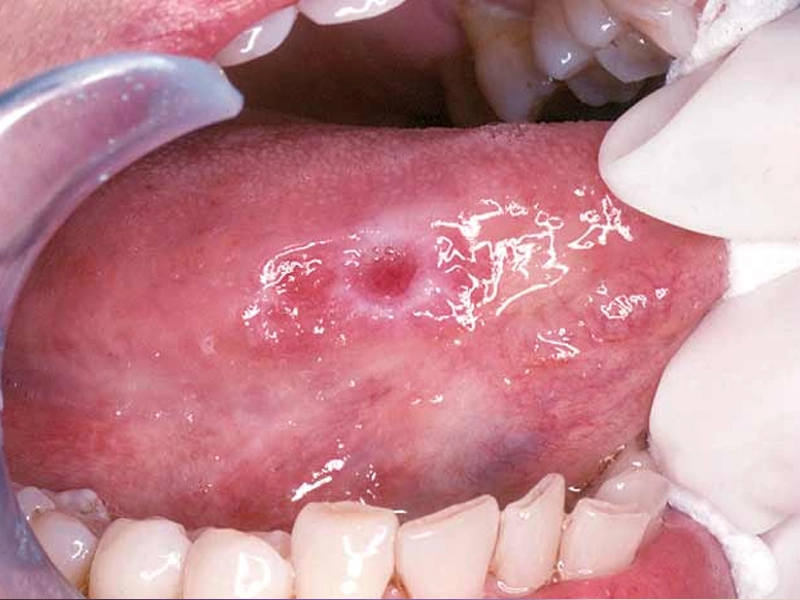

Visual Inspection

Our dentist will look for any asymmetries, swellings, bumps, patches of color, ulcerations, or other abnormalities in the mouth, face, neck, and oral cavity.